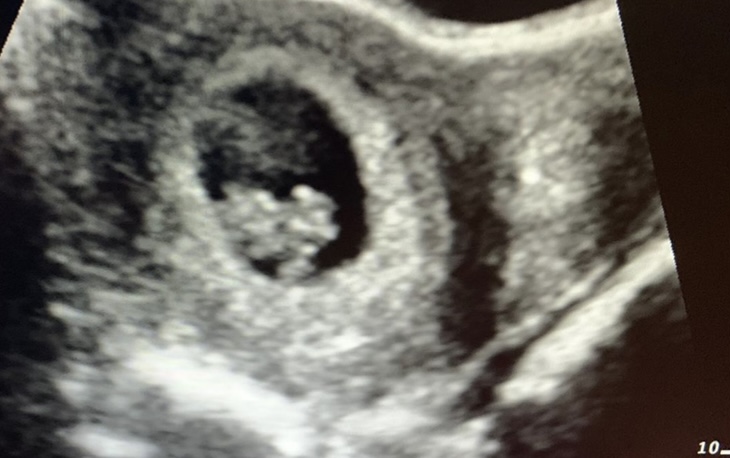

Děvčata dnes jsem byla na kontrole. A vše v pořádku🥰 miminko je tam kde má být🤗 tluče i srdíčko❤️